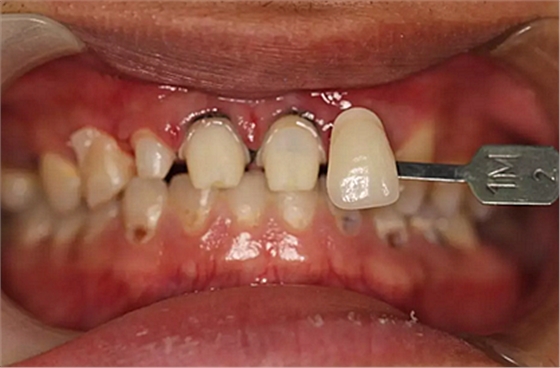

兩周后,主人帶我們往醫(yī)院拆線,取模,比色,為我們重新量身定制了一套堅(jiān)固的“外套”。

第5次復(fù)診的時(shí)候,終于讓我們4個(gè)兄弟恢復(fù)了正常的容顏。